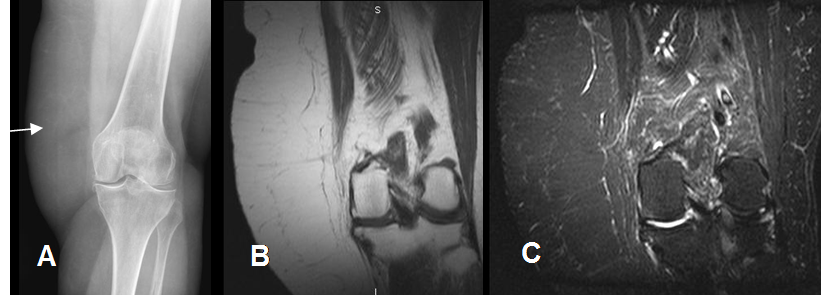

A: Rx AP y B: RM coronal en T1 y C: RM coronal en STIR. Gran prominencia en los tejidos blandos de la parte lateral de la rodilla, por tejido graso que corresponde a lipoma no encapsulado.